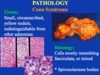

Conn syndrome

aldosterone producing adenoma - primary hyperaldosteronism

indistinguishable from other adenomas

small yellow circumscribed nodule, indstinguishable from others

cells mostly resemble fasiculata or mixed